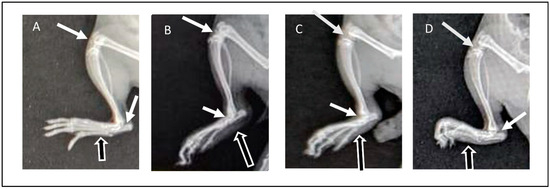

2.13.5. Assessment of Radiographic Images

3.8.4. Assessment of Radiographic Images